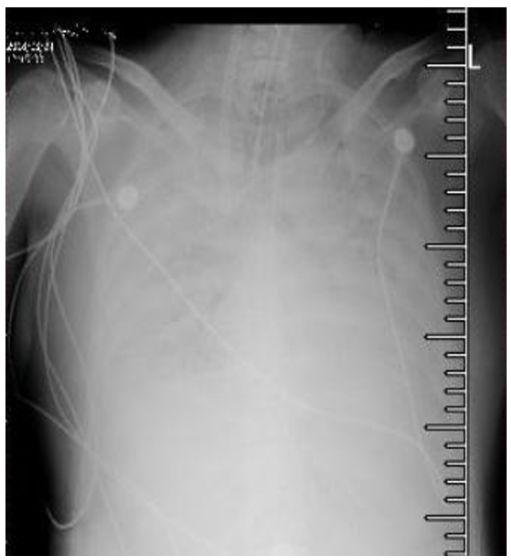

8月5日~8月9日这四天的胸部影像学进展很快,尽管已经接受了积极的抗感染治疗(三代头孢、左氧等),无好转。那么这样的病例是耐药细菌感染吗?

临床CAP病例诊治经过

转入我院后,有病毒检测平台,检测出FluA阳性,我们还做了恢复期抗体也是4倍增高,所以这是一个确诊为FluA感染的病例。后来由于有明确的病毒感染,就没有使用太多的抗菌药物。病人于8月16日好转出院。

这个病例告诉我们,在CAP中,尤其是对起始的抗感染治疗无效的病例里面,存在病毒感染。